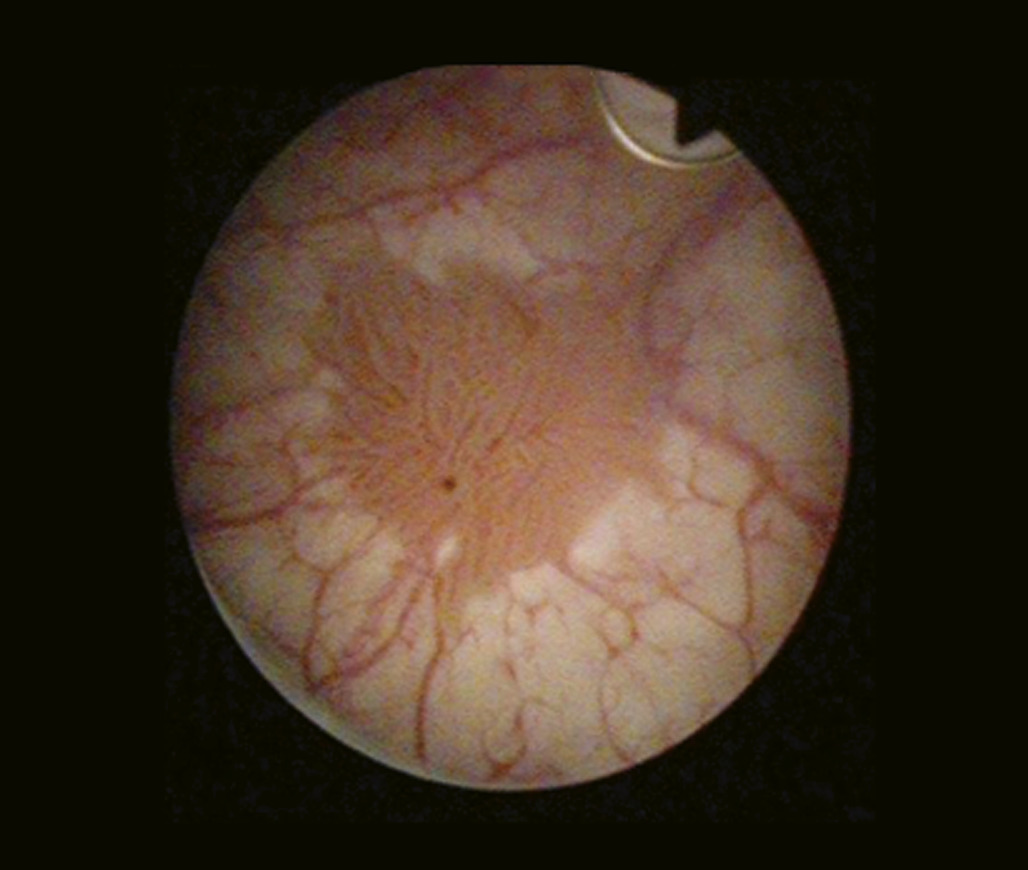

Urétro-cystoscopie

L’urétro-cystocopie, ou fibroscopie vésicale, permet l’exploration endoscopique de la vessie (fig. 3). Elle est réalisée en consultation sous anesthésie locale, après vérification de la stérilité des urines et permet de confirmer la présence d’une tumeur de vessie mais aussi de préciser le nombre, la taille, la topographie et l’aspect de la tumeur (papillaire, sessile, ou plage érythémateuse en cas de carcinome in situ). Elle permet aussi d’éliminer les diagnostics différentiels de tumeur vésicale en échographie, notamment l’existence d’un caillot sanguin intra-vésical.